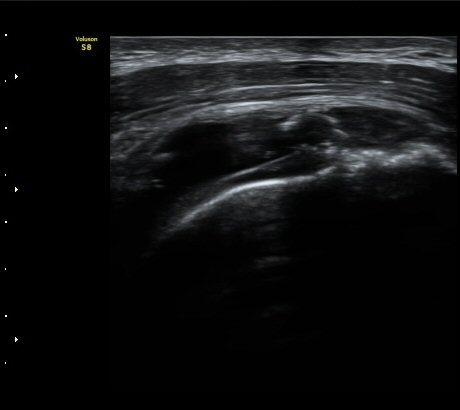

°ß°©ÇÏ±Ù°Ç Á¾´Ü¸é°Ë»ç¿¡¼­ ÀÌ»ó ¼Ò°ßÀ» º¸ÀÌÁö ¾Ê´Â´Ù(»çÁø 2)